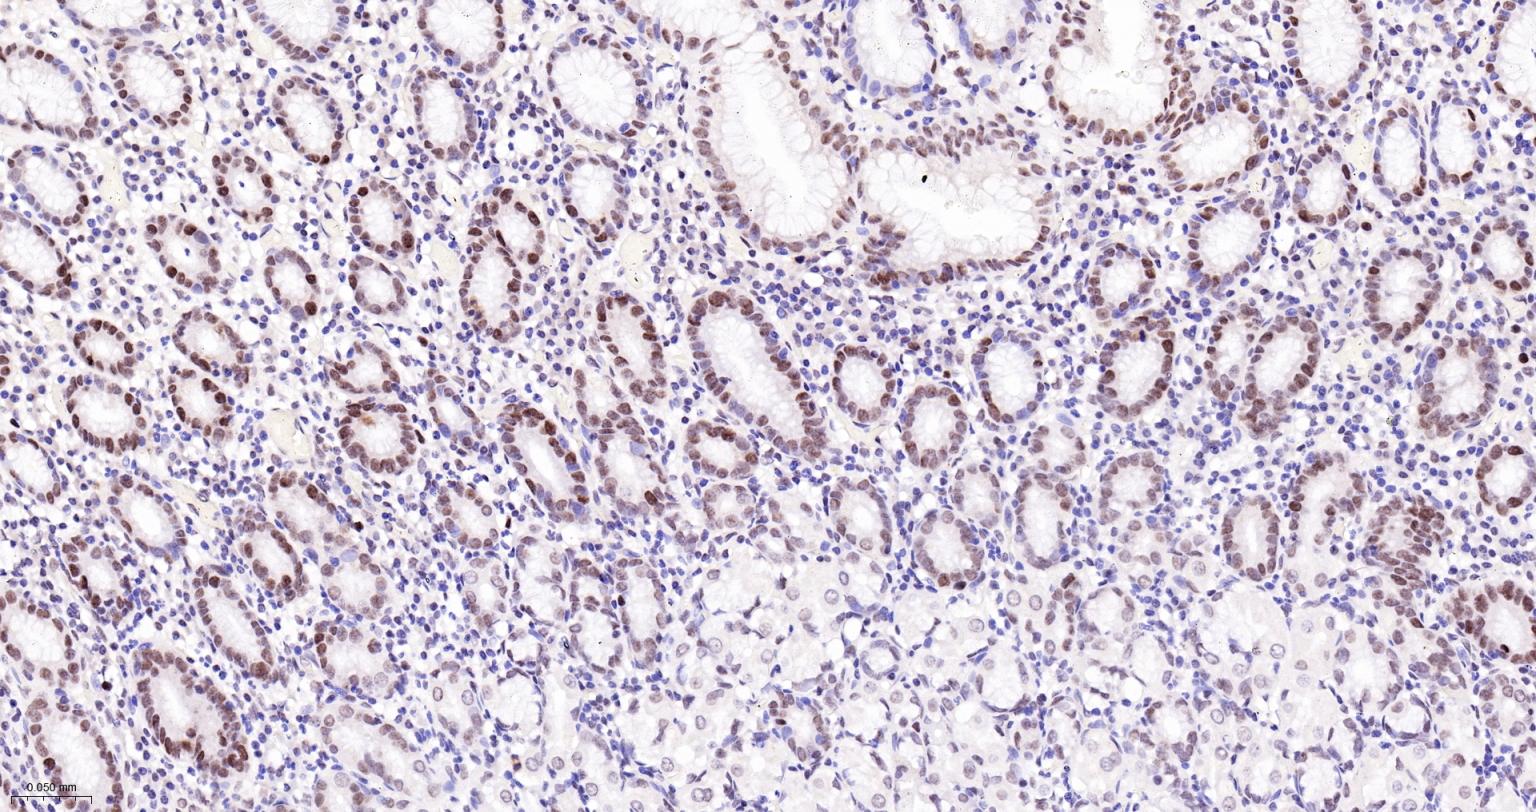

Paraformaldehyde-fixed, paraffin embedded Human Stomach; Antigen retrieval by boiling in sodium citrate buffer (pH6.0) for 15 min; The section was incubated with CDCA5 Monoclonal Antibody, Unconjugated (bsm-61346R) at 1:200 overnight at 4°C, followed by conjugation to the bs-0295G-HRP and DAB (C-0010) staining.